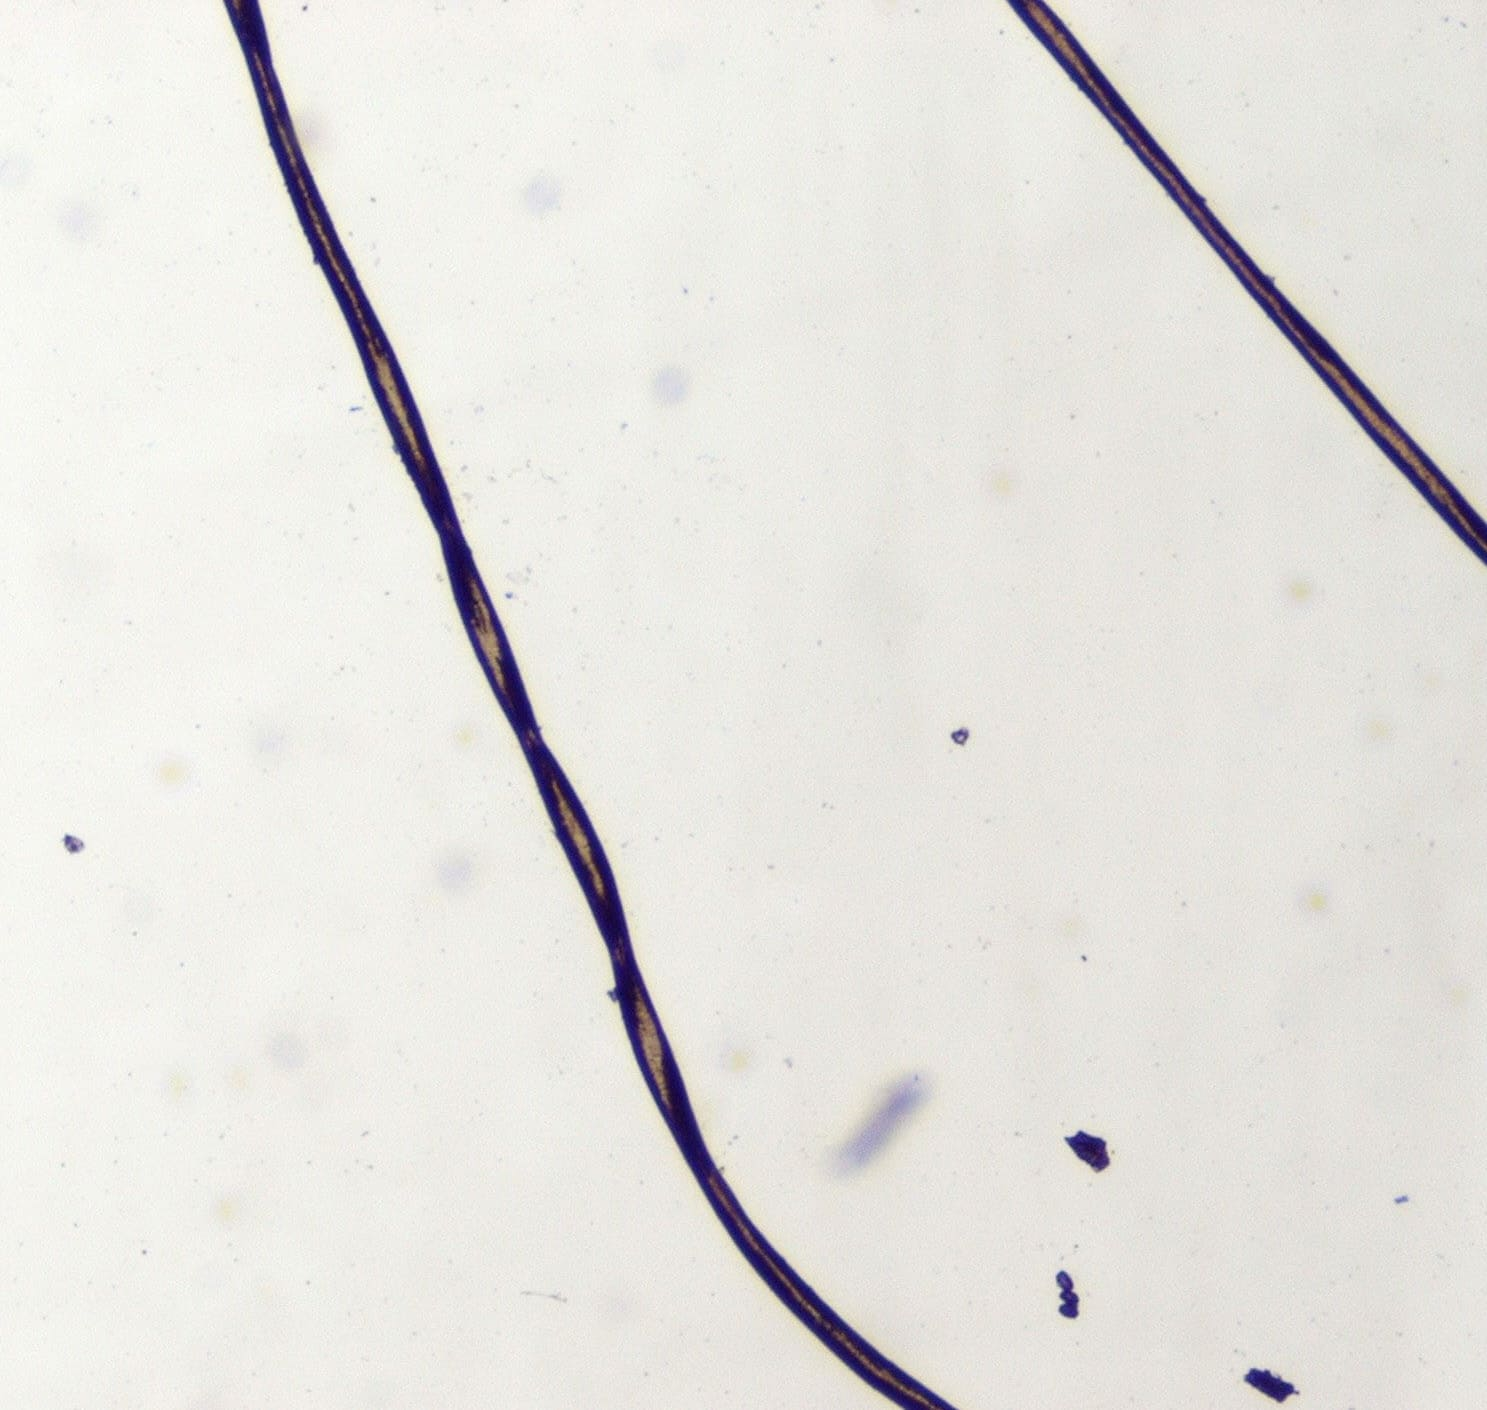

The short and brittle hairs in patients with pili torti, when viewed through a microscope, appear flattened and twisted through 90° to 360°. The twisting must be differentiated from the normal twisting in the hair of black individuals and in the pubic/axillary hairs of other races; the hairs are distinguished by the multiple irregular intervals of twisting along an otherwise straight hair shaft . As with trichorrhexis nodosa, pili torti does not signify a particular abnormality but can be seen in many different syndromes and in the presence of other hair shaft abnormalities. Hereditary pili torti as an isolated finding, usually autosomal dominant, but potentially autosomal recessive or sporadic, is present at birth or develops over the first 2 years of life . Clinically, the patient may have patchy alopecia with coarse stubble or longer broken hairs. The hair abnormality may improve after puberty. Pili torti, or a facsimile best characterized as “twisting hair dystrophy,” may occur with other abnormalities. Particularly notable is the association of pili torti with Menkes syndrome (which results from inherited loss-of-function mutations in the gene encoding a copper-transporting adenosine triphosphatase (Atp7a) on the X chromosome or trichopoliodystrophy. Infants with Menkes syndrome develop sparse, depigmented brittle hairs that show pili torti or trichorrhexis nodosa on microscopic examination. The affected child characteristically has pale, lax skin, and mental and neurologic impairment secondary to degeneration of cerebral, cerebellar, and connective tissue. In this X-linked recessive disorder, the defective gene, MKN or ATP7A, which maps to Xq13.3, encodes a copper-translocating membrane protein adenosine triphosphatase that prevents effective copper transport and leads to the accumulation of intracellular copper in